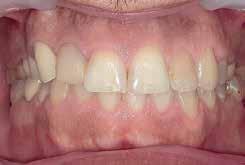

Case 1:

A 24-year-old female presented to the orthodontic clinic with the chief complaint of “Presence of space in the posterior mandibular right region”.

An intra- oral examination revealed the absence of the mandibular right first molar, tilting and oblique inclination of the mandibular second and third molar.

The patient had skeletal and dental class I, a normal overbite an overjet, slight mandibular anterior crowding, rotation of lower right first and second premolars, impaction of upper left and right third molars, and mandibular left third molar.

The patient recalls an extraction that was carried out during childhood but couldn’t specify exactly if it was the mandibular right first molar.

A panoramic x-ray showed the absence of the right first mandibular molar, a 45 degrees inclination of the second and third mandibular right molars, a vertical bone defect at the old extraction site, with a large composite filling on a endodontically treated mandibular left first molar.

Non extraction treatment, with mesial root movement and protraction of the mandibular second and third molars in order to close the residual space, create a solid contact between the mandibular second molar and second premolar without the need for prosthetic dental implant or crown. This option would require longer orthodontic treatment time with extensive follow up visits, however no extra cost is allocated for surgical and prosthetic procedures. (Figures 1 and 2)